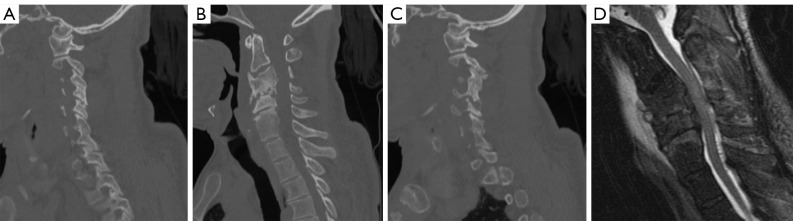

Case description: We present a medically complex 58-year-old male who developed a severe combined kyphotic and coronal cervical deformity in a delayed fashion after an initial posterior cervical decompression for symptomatic epidural abscess associated with VO. The patient underwent a combined two-stage anterior and posterior approach. The patient tolerated both surgeries without complication and follow-up imaging demonstrated correction of cervical sagittal and coronal alignment. Interestingly, despite appropriate antibiotic therapy, intraoperative culture during deformity correction yielded growth of the initial culprit microorganism.

Conclusions: A two-stage anterior and posterior approach with multi-level anterior cervical decompression and instrumented fusion followed by posterior cervicothoracic instrumented fusion addresses the primary surgical goals of affected spinal segment decompression, restoration of appropriate spinal alignment, and prevention of further deformity or neurologic compromise. This report highlights suitability of techniques accessible to most spinal surgeons for correction of a multiplanar deformity, contributes to the ongoing discussion regarding instrumentation in the setting of an active spinal infection, and emphasizes the importance of close clinical and radiographic follow-up in this patient population.